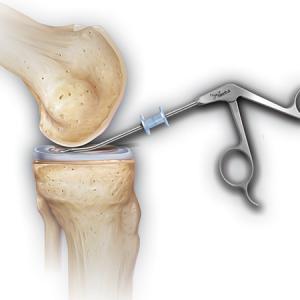

Operative Therapie: Meniskusteilentfernung

Wenn der verletzte Meniskus so aufgefasert ist, dass eine Meniskusnaht nicht mehr in Frage kommt, wird der verletzte Teil des Meniskus entfernt. In den häufigsten Fällen betrifft dies den hinteren Anteil des Innenmeniskus, seltener den eher folgeschwereren Außenmeniskus. Eine Meniskusteilentfernung wird heutzutage nur noch arthroskopisch mit Spezialscheren, -stanzen und -schleifer durchgeführt, so dass die Schmerzen verschwindend gering sind. Hierbei ist es wichtig, dass nur so viel Meniskusgewebe entfernt werden sollte, wie unbedingt notwendig ist.